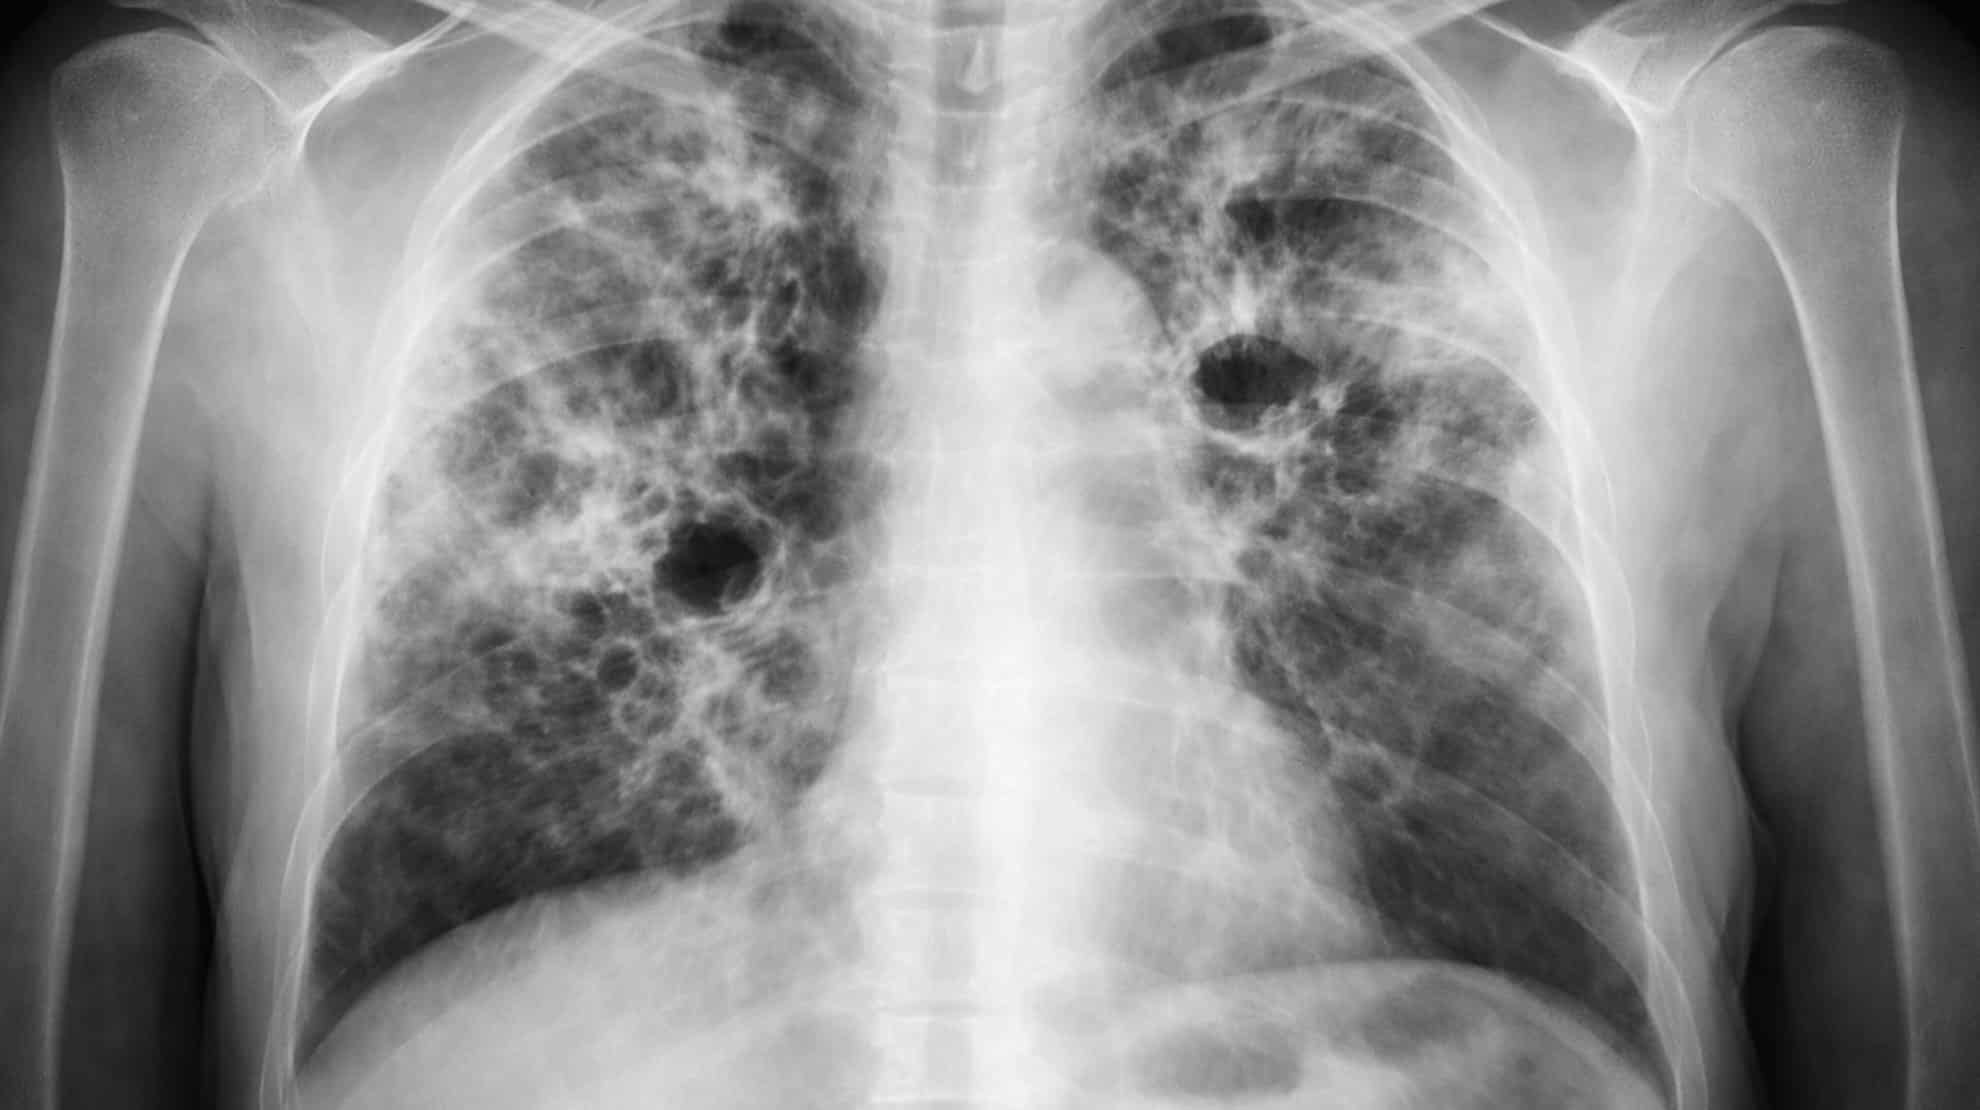

Vorig jaar meer gevallen van tuberculose in Nederland